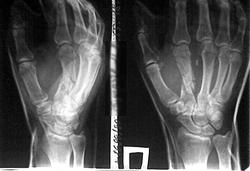

Травма на работе, такой вот перелом. Извините за качество, на телефон снимал старой модели.

Как можно описать перелом? Внутри - двух - суставной, раздробленный на большом протяжении, множественно-оскольчатый перелом второй пястной кости. Или просто - сложный краш-перелом? Переломы головок 1-й и 3-й пястных костей тоже могут быть.

Сложный многооскольчатый перелом второй пястной кости.

Нет, не пресс. Циркулярка. Рука на диск сорвалась.

Насчет 1 и 3 пястных - это световое суммирование пикселей экрана, тождественное низкому разрешению матрицы камеры дешевого телефона, вводящее наблюдателя в заблуждение по поводу тех или иных неконтрастных изменений на картинке, создаваемой этими же пикселями экрана. Пардон за многословие, настроение лирическое, я сегодня Пелевина читаю.

Чего не знаю, того не знаю. Кистовидная дегенерация, может от хронического перегруза: мужик рабочий.